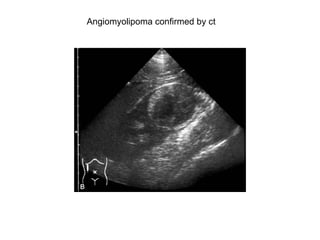

Angiomyolipoma

Angiomyolipoma confirmed by ct